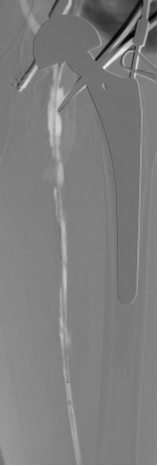

图为:左股动脉内膜剥脱

图为:支架植入

图为:术后造影